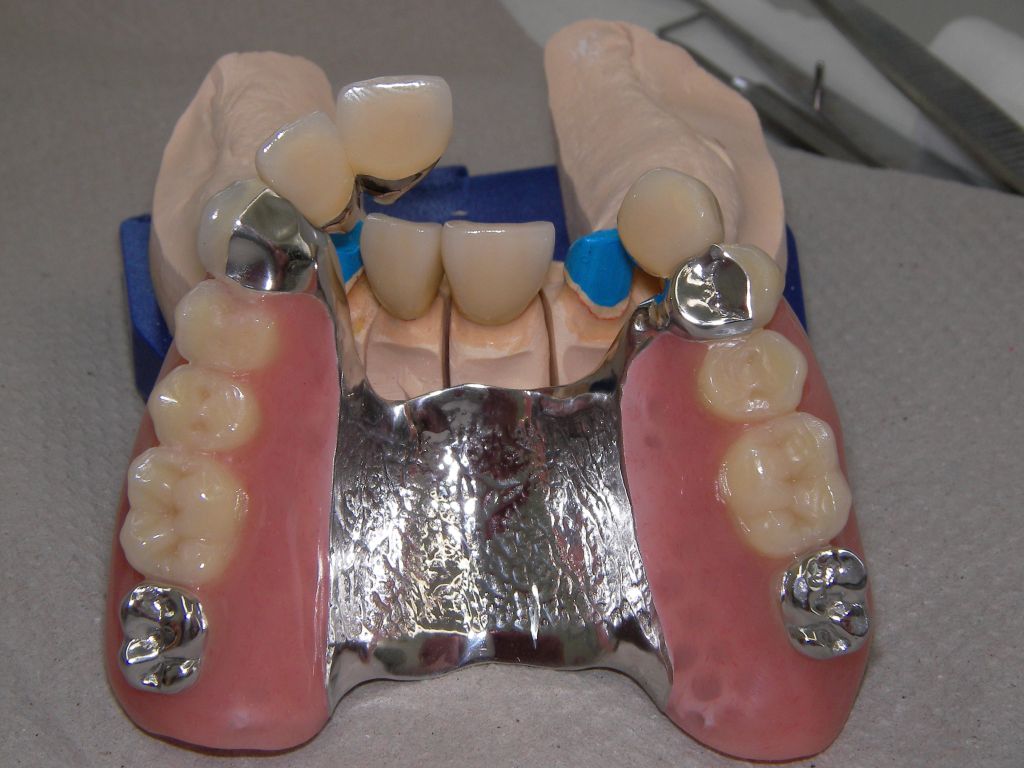

Die Bilder können alle angeklickt werden! Das Hauptproblem dieses Falles lag im Oberkiefer - die über die Jahrzehnte abgeknirschten, kurzen Zähne erschweren Kronen, die durch eine Prothese belastet werden können. Die gewählte Lösung besteht darin, die Zähne nur rundherum zu beschleifen, aber nicht mehr zu kürzen und die Prothese mit einem Druckknopfsystem an die Zähne anzukoppeln, das ein "Spiel" aufweist, so daß die Prothese nicht als Hebelarm auf die schwachen Restzähne wirken kann. Rechts die beschliffenen Zähne kurz vorm Zementieren der Kronen. |

Die Unterseite, die später der Mundschleimhaut aufliegt, ist im Bereich der Druckknöpfe hochglanzpoliert und damit gut pflegbar, was wichtig für gesundes Zahnfleisch an diesen Stellen ist. Das Kugelattachment (Druckknopf) ist das Preci-Clix (Fa. Ceka). |

Die Zähne auf der Prothese sind aus verarbeitungstechnischen Gründen auch heute meist noch aus Kunststoff, auch wenn teurere Keramikzähne möglich wären. Kunststoff verschleißt über die Jahre, der Biß verändert sich. Um letzteres zu verhindern, sind hier zusätzlich Metallkauflächen eingearbeitet, die sich nicht verändern werden. Auch Verbindungselemente verschleißen. Um den Verschleiß reparieren zu können, sollte der Verschleiß aus dem Mund in die Prothese gelenkt werden. Im Mund deshalb hier 4 harte Titankugeln, die passenden Druckknöpfe in der Prothese aus Kunststoff, wo sie leicht ausgewechselt werden können. | |

Links Bilder des Oberkiefers, rechts des Unterkiefers. Die Arbeit wurde von dem Dentallabor "Heitmeyer Zahntechnik", Osnabrück, gefertigt. Dem Labor ist hier für die hervorragende Arbeit zu danken, dem Patienten für die Freigabe der Bilder! |